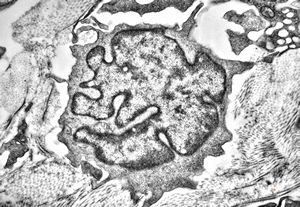

F, 85y. | Merkel cell tumor